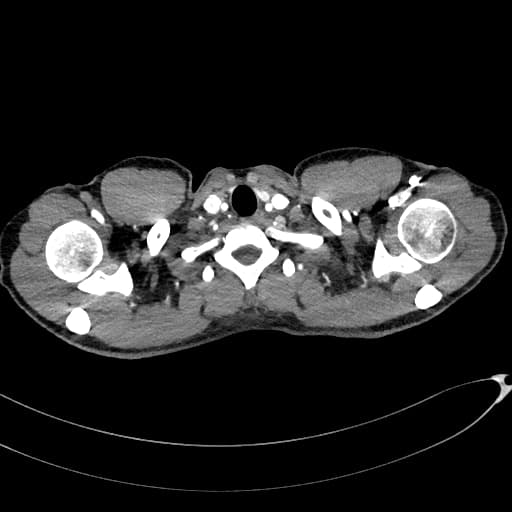

Chẩn đoán & Phát hiện

Thành dạ dày dày không đối xứng và tăng quang mạnh do thâm nhiễm u tại tâm vị và phần gần bờ cong nhỏ, kèm theo nhiều hạch bạch huyết lớn quanh dạ dày. Các hạch bạch huyết lớn này tiếp xúc sát với thùy gan trái và tuyến thượng thận trái, cùng với tình trạng tuyến thượng thận trái lớn nhẹ, gợi ý có sự xâm lấn tại chỗ. Có một hạch bạch huyết lớn nằm ở chuỗi hạch dưới hoành phải. Ngoài ra, có một khối lớn, không đồng nhất với bờ không đều ở gan, biểu hiện tăng quang ngoại vi sớm kèm washout muộn và hoại tử trung tâm rộng. Có tình trạng giãn nhẹ ống mật trong gan ở vùng ngoại vi của khối u. Phần còn lại của gan bình thường và không có dấu hiệu của xơ gan nền. Có một nang kích thước 8 mm ở lách. Một vài nang nhỏ cạnh bể thận được ghi nhận ở cả hai thận, quan sát rõ hơn trên các hình ảnh thì bài tiết. Bệnh nhân đã được thực hiện sinh thiết khối u dạ dày qua nội soi và sinh thiết kim lõi khối u gan dưới hướng dẫn siêu âm. Kết quả giải phẫu bệnh và hóa mô miễn dịch xác nhận ung thư biểu mô tuyến dạng tế bào gan nguyên phát của dạ dày kèm di căn gan. THẢO LUẬN: Trường hợp này minh họa một ca ung thư biểu mô tuyến dạng tế bào gan tiến triển ác tính của dạ dày, xuất phát từ tâm vị và phần gần bờ cong nhỏ ở một bệnh nhân lớn tuổi, biểu hiện với di căn hạch vùng tiến triển và di căn gan lớn, nồng độ AFP huyết thanh cao, cùng các đặc điểm hình ảnh có thể rất giống với ung thư biểu mô tế bào gan nguyên phát. Ung thư biểu mô tuyến dạng tế bào gan của dạ dày là một loại ung thư dạ dày hiếm gặp, có độ ác tính cao, về mặt mô học giống với ung thư biểu mô tế bào gan và thường sản sinh alpha-fetoprotein (AFP). Nó chiếm khoảng 1% các trường hợp ung thư dạ dày và thường được phát hiện ở giai đoạn muộn với di căn gan và di căn hạch. Ung thư biểu mô tế bào gan nguyên phát và ung thư biểu mô tuyến dạng tế bào gan của dạ dày di căn gan có thể có hình thái rất giống nhau; tuy nhiên, chúng khác nhau về bối cảnh lâm sàng, đặc điểm hình thái và hóa mô miễn dịch.